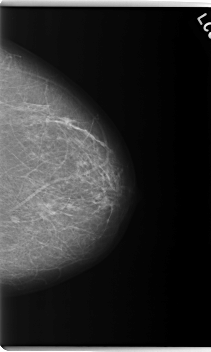

C_0174_1.LEFT_MLO

C_0174_1.LEFT_CC

LEFT_CC LINES 5976 PIXELS_PER_LINE 3576 BITS_PER_PIXEL 12 RESOLUTION 50 NON_OVERLAY

LEFT_MLO LINES 5912 PIXELS_PER_LINE 3512 BITS_PER_PIXEL 12 RESOLUTION 50 NON_OVERLAY